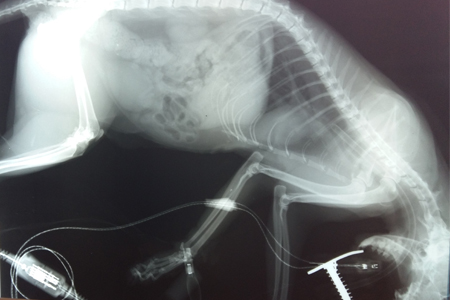

Рентгенография — исследование внутренней структуры объектов, которые проецируются при помощи рентгеновских лучей на специальную плёнку, бумагу или другой носитель. Наиболее часто термин относится к медицинскому неинвазивному исследованию, основанному на получении суммационного проекционного изображения анатомических структур организма посредством прохождения через них рентгеновских лучей и регистрации степени ослабления рентгеновского излучения.

При помощи рентгена можно исследовать патологии грудной полости (сердце, легкие, пищевод), брюшной полости кишечник, печень мочевой пузырь и другие органы, опорно-двигательный аппарат. Ценную информацию предоставляют нам снимки с введением рентгеноконтрастного вещества (ангиография, миелография).